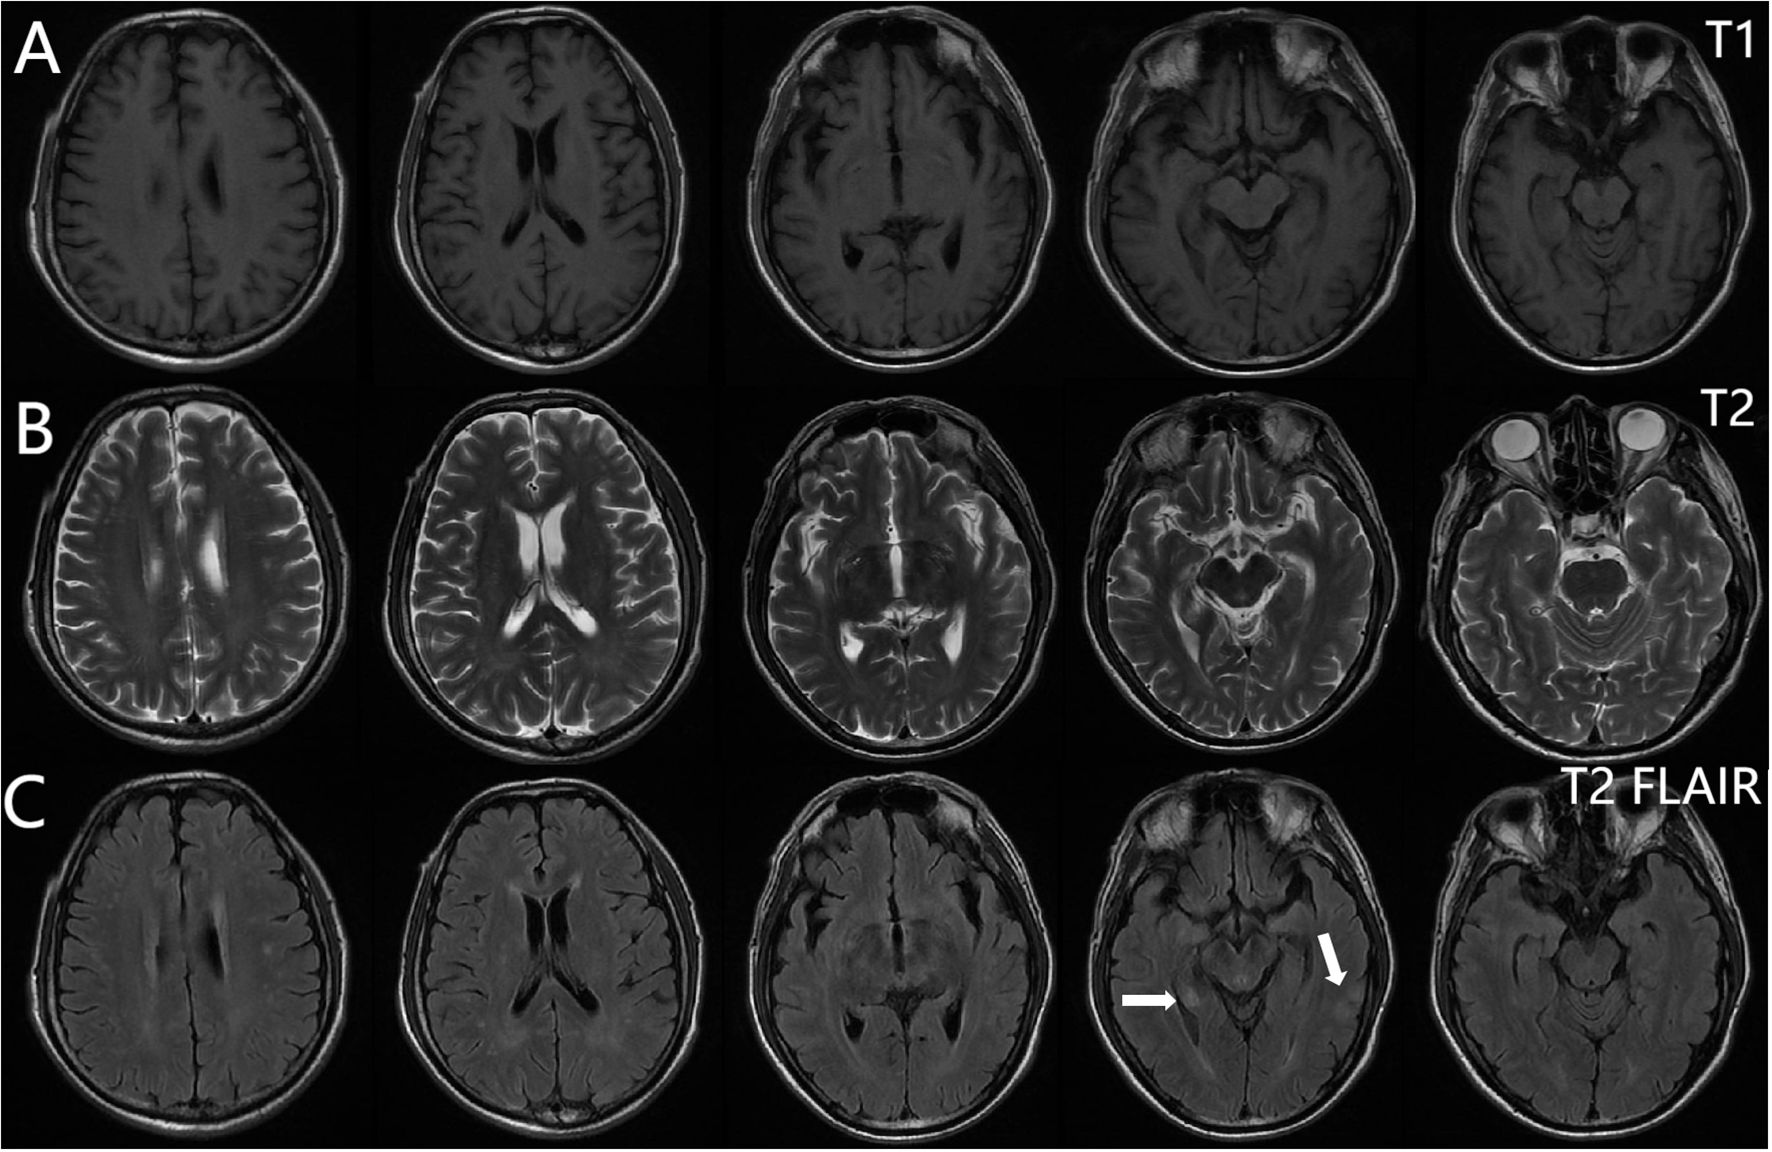

From 8 April, the clinical symptoms demonstrated progressive improvement, marked by the patient’s transition from stupor to drowsiness on a consciousness scale. By 16 April the patient was alert and attentive to these questions. A high dose of methylprednisolone was administered for 5 days and the dose was subsequently decreased gradually. Dehydration was implemented to reduce intracranial pressure. Another lumbar puncture was performed on the tenth day of admission (15 April). CSF analysis revealed normal glucose levels with elevated protein (0.89 g/L). The leukocyte count in the CSF was 78×106/L, representing a significant decrease compared to the WBC count in the CSF on 4 April. MOG-IgG in the CSF and serum was negative, and GFAP-IgG in the CSF was negative. The serum IgG decreased to 3.21 g/L, reflecting a 56% reduction compared with the previous serum IgG level. Another cranial MRI was performed on 3 April. The T2 FLAIR showed multiple hyperintensities in the posterior horn of the lateral ventricle, medial temporal lobe, and temporal cortex (Figures 2, 3). After tapering the corticosteroid therapy, the patient was transitioned to oral administration. He was discharged from the hospital on 18 April with a notable improvement in symptoms. At the one-month post-discharge outpatient follow-up visit, all psychiatric symptoms had disappeared completely. Treatment included low-dose oral steroids and mycophenolate mofetil. Three months after discharge, the patient underwent cranial MRI, which showed that the multiple hyperintensities in the medial temporal lobe and temporal cortex had decreased (Figure 4). Ten months after the patient’s initial presentation, no symptoms except for cognitive impairment were observed, and no drug-related adverse reactions were reported, with the patient reporting an “irritable mood” (MMSE: 26, MOCA: 13, HAMA: 5, HAMD: 1). The impaired dimensions included visual-spatial function, execution, and memory.

MRI brain scans in three sequences: T1, T2, and T2 FLAIR. Row A displays T1-weighted images with reduced contrast. Row B shows T2-weighted images with higher fluid contrast. Row C presents T2 FLAIR images highlighting certain regions with arrows.

Figure 2. Brain magnetic resonance imaging. T1-weighted (A), T2-weighted (B), T2 FLAIR (C). Multiple punctate lesions with T1 hypointensity, T2 hyperintensity, and FLAIR hyperintensity in the centrum semiovale, periventricular white matter, and basal ganglia regions.